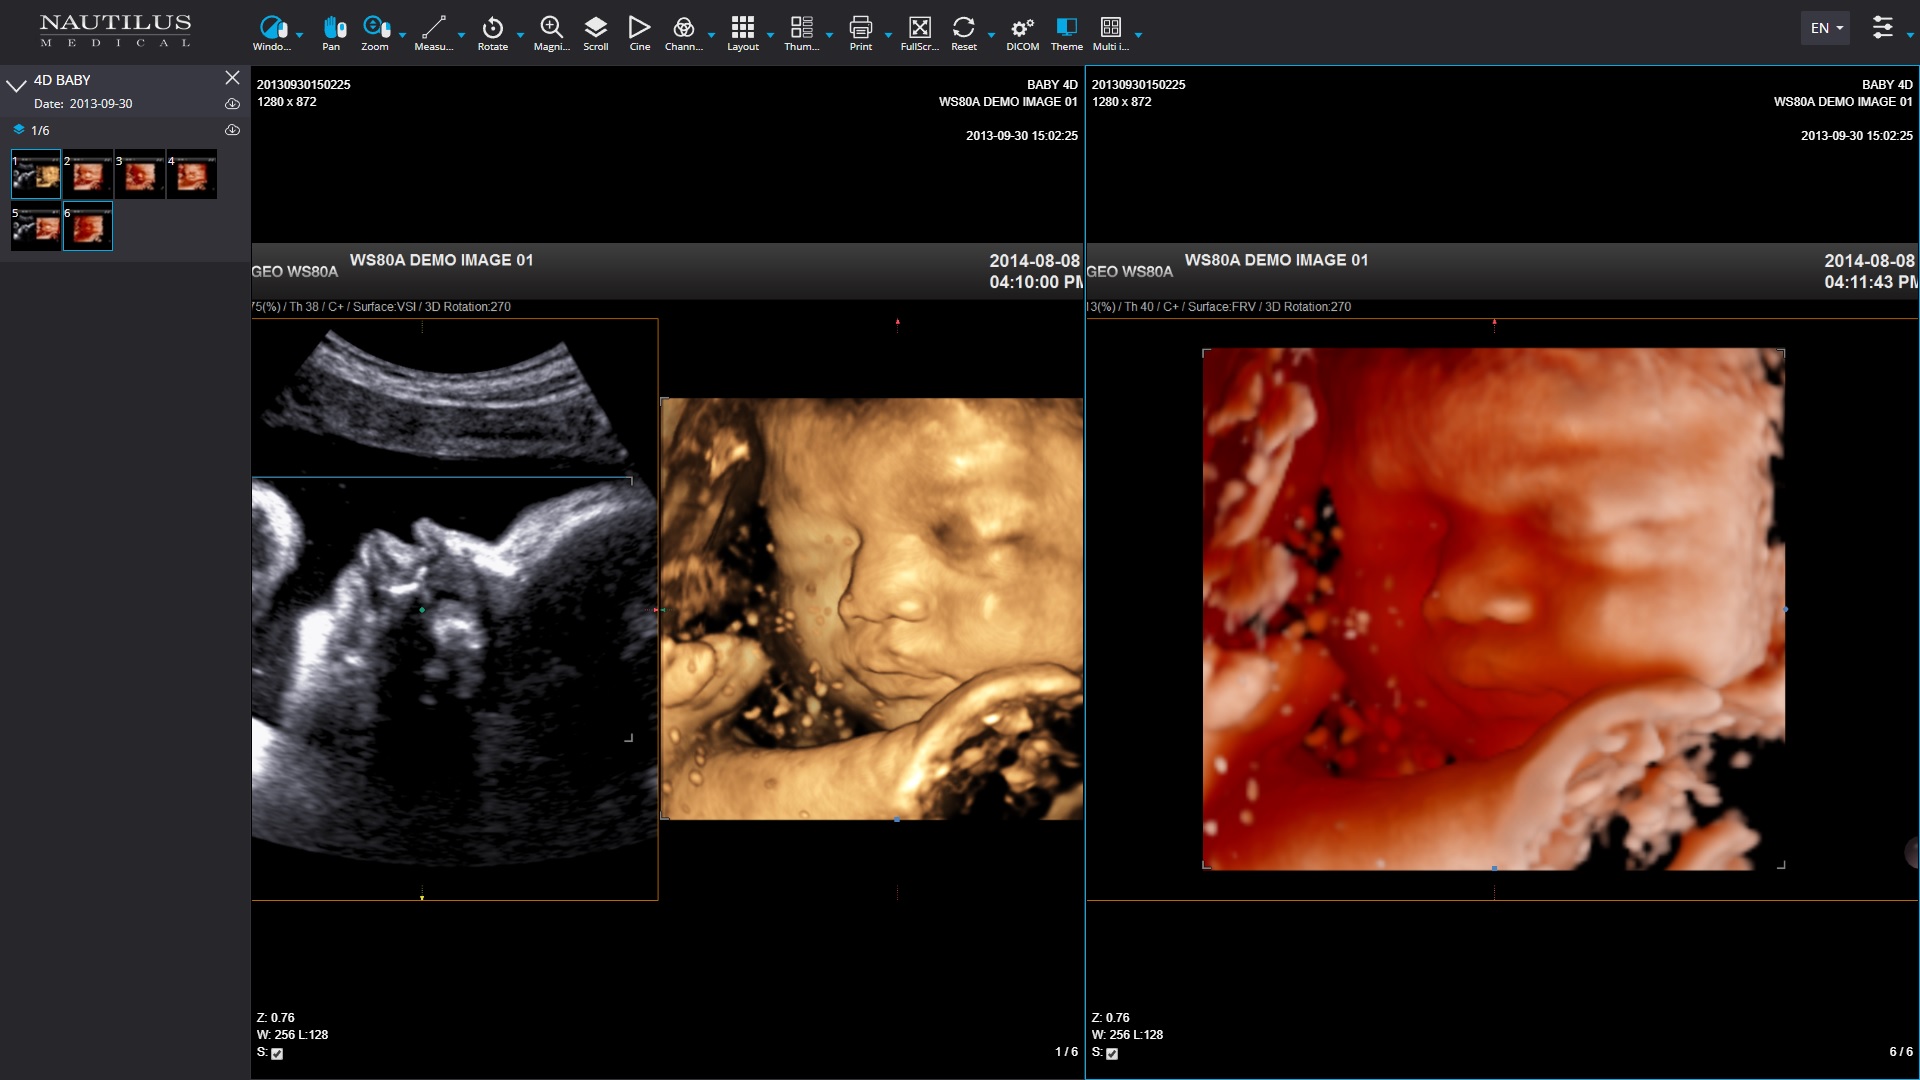

Gaining access to a specialist will become more and more difficult. Technology can be a saving grace in getting more specialists in front of and caring for more patients without risk of exposure and much higher efficiency. Nautilus Medical is a company solving these issues in telehealth with a technology called TeleRay. This platform delivers face to face consultation while viewing the patient and imaging in real-time. It provides quality by utilizing peer to peer connections and high-speed cellular networks when bandwidth is low. Physicians may review real-time imaging that is taking place in the field, rural areas, and practices outside of their local area- or anywhere in the world! The Association of American Medical Colleges (AAMC) acknowledged this fact in its most recent physician supply report, which projects a shortage of up to 67,000 specialists by 2032. The Review further suggests that the use of value-based physician payments is gaining momentum. Of those Merritt Hawkins clients offering physicians a production bonus last year, 56% were based in whole or in part on value-based metrics such as patient satisfaction and outcome measures, up from 43% the previous year.

Timothy Kelley, CEO of Nautilus, said, "doctors and specialists can use TeleRay in many situations." He explained that TeleRay could view modalities such as ultrasound in real-time from remote locations. He said, "Emergency responders, maternal-fetal medicine doctors, cardiologists, and more can view the patient, the modality, and speak to the sonographer or technologist to get results that matter." Ultrasounds can determine internal bleeding, injuries, and fractures miles away.

Nautilus Medical COO Steve Austin likes to talk about the platform's advantages, including the storage, sharing, and access to images after they are captured. "This gives immediate access with real-time tools to make a diagnosis from anywhere on any device." He continued, "Its prime time for a platform like this that combines telehealth with radiology, TeleRay is the only platform that offers real-time viewing of the modalities which can be critical in high-risk situations where a specialist can virtually look over the shoulder of the sonographer or technologist as if they're in the room to adjust, view, and consult."